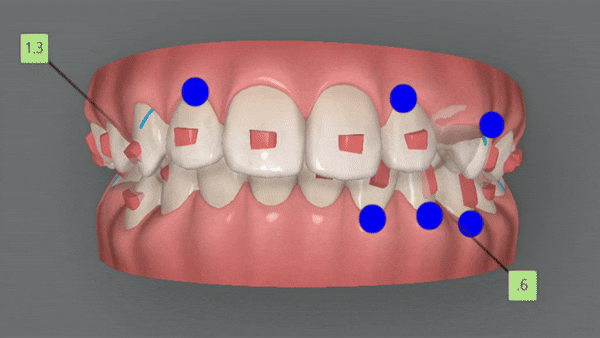

1st (40개)

첫번째 클린체크의 영상입니다.

인비절라인의 장점 중의 하나는

교정 후의 모습을 예측할 수 있는것 입니다.

원장님께서 클린체크 디자인을 마치게 되면

인비절라인 교정치료 후에

치아이동이 어떻게 변화하는지 클린체크를 통해 확인 해 볼 수 있는것인데요.

클린체크대로

치아들이 움직이면서 점점 가지런해 지는게 보이시나요?

첫번째 클린체크에서는 총 40개의 장치로

진행 해드렸습니다.

청소년인비절라인

유펜바른치과에서

인비절라인 단 40개의 장치로

악궁이 확장되면서 뻐드러져 있던 송곳니가 제 위치를 찾으며

자리를 잡아 가지런해졌습니다.